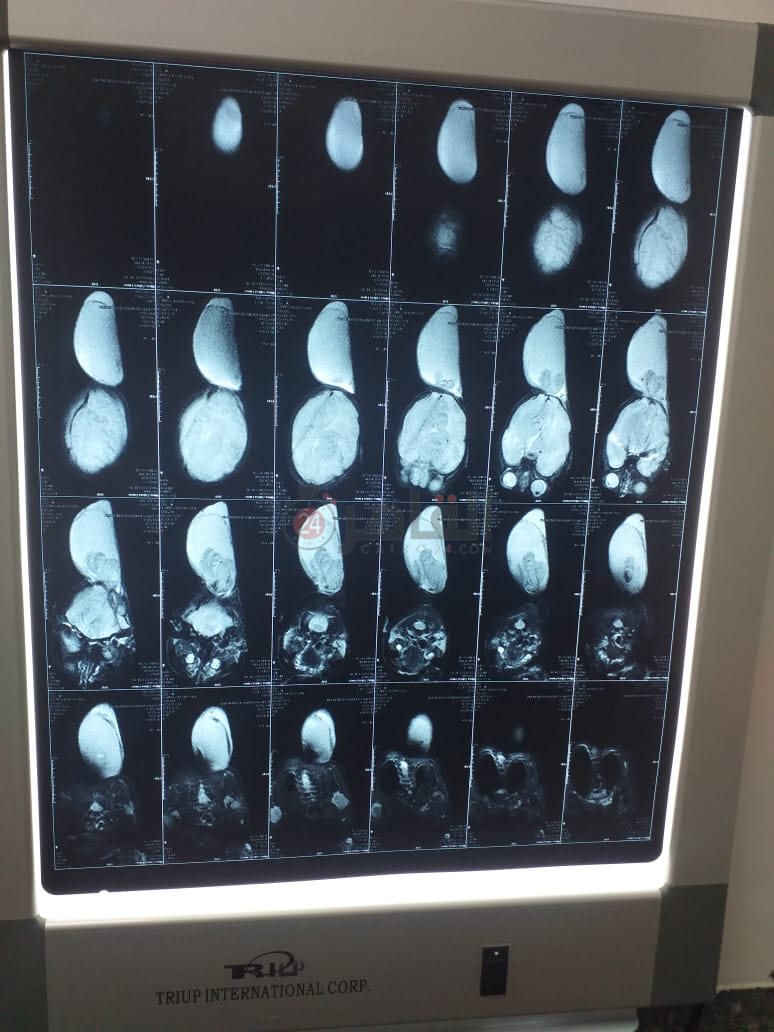

وأكمل زكريا لويس: أجرينا أشعة رنين على رأسه، وتبين حجم الكيس، وما بداخله مياه مع جزء من المخ، وأكد الأطباء ضرورة إجراء عملية جراحية لإزالة الكيس، وطلبنا تحويله من التأمين الصحي في أسوان، على مستشفى أطفال مصر، لكن عندما حضرنها إلى المستشفى؛ أخبرونا بعدم وجود حضَّانة، ولا بد ان ننتظر حتى تتوفر واحدة، والطبيب شدد على الإسراع في إجراء العملية الجراحية بحد أقصى شهر حفاظا على حياة ابني.

وأشار والد الطفل إلى أنه توجه للعديد من المستشفيات في القاهرة، وأجرى أشعة جديدة على رأس الطفل، حيث أكد أحد المستشفيات أنه لا بد من الانتظار شهرين على الأقل، مضيفًا: في مستشفيات قالوا لازم نستنى عشان الجلد يكبر ويكون سميك، لكن حاليًا ظهرت تقرحات على الكيس، وممكن يتفتح بسهولة، وساعتها ابنى هيموت.